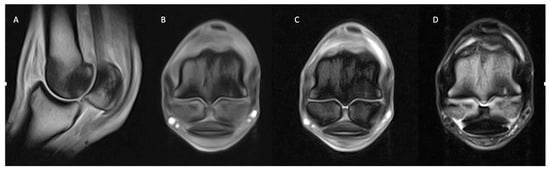

3.2.1. Osseous Pathology

3.2.2. Joint Pathology

3.2.3. Soft Tissue Pathology